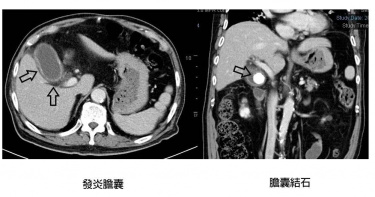

85歲姓男子有高血壓、糖尿病及慢性腎病的病史,上月因發燒及右上腹痛到亞東醫院急診就醫,經電腦斷層掃描後發現一顆3公分大且硬的膽結石及急性發炎。因患者年紀大又具有慢性疾病麻醉及開刀風險較高,經評估後轉介至亞東醫院超音波暨內視鏡中心由鍾承軒主任執術,利用經口內視鏡超音波導引,放入雙翼官腔吻合金屬支架進入膽囊內,將膽囊內發炎感染的積液引流至腸胃道內,配合電動液壓及碎石金屬網將結石碎掉取出,3-4週後再使用胃鏡將金屬支架取出達到「保膽取石」治療效果,因病人無須開刀,術後痊癒很快。急性膽囊炎是膽結石常見的併發症,而外科開刀切除膽囊是急性膽囊炎的治療首選方式,然而隨著台灣逐漸高齡化,使得許多老年人尤其合併有慢性疾病者,倘若發生膽結石合併急性膽囊炎時,其外科開刀及全身麻醉的風險增加,只能暫時性地使用經皮穿肝置放塑膠外引流管將膽囊內發炎感染的膽汁積液排出並配合抗生素來治療,鍾承軒主任說明,這樣的治療方式無法取出膽結石,且外引流管的滑脫以及拔除後會有反覆發炎的狀況,治標不治本。內視鏡超音波導引金屬支架進入膽囊內,將膽囊內發炎感染的積液引流至腸胃道內,配合電動液壓及碎石金屬網將結石碎掉取出。(圖/亞東醫院提供)鍾承軒主任表示,近年來隨著內視鏡醫療儀器及技術的進步,許多經自然孔洞(如口、肛等)的微創內視鏡技術可以取代傳統外科侵入性手術治療許多疾病,尤其是內視鏡超音波在膽胰疾病上的應用,除了疾病的診斷以外,也在腸胃道管腔內執行超音波導引,來做內引流治療,並同步配合較大管腔的金屬支架置放術,可以建立不同器官之間的人造廔管來增加內視鏡治療的空間。雖然內視鏡超音波相比過往療程療效更佳,但鍾承軒主任仍提醒,目前健保尚未給付相關治療,此外在急性膽囊炎的應用只適用於經外科醫師評估無法開刀治療之患者,因此若有出現相似徵狀,需與主治醫師討論評估其可行性,方能執行手術。